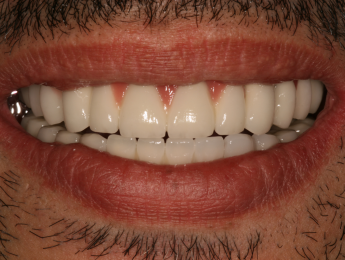

- A fogászati implantátum természetes hatást kelt, ezért senki sem fogja észrevenni, hogy nem eredetiek a fogai. Még Ön sem fogja érzékelni a különbséget.

- Újra természetes, gyönyörű mosoly.